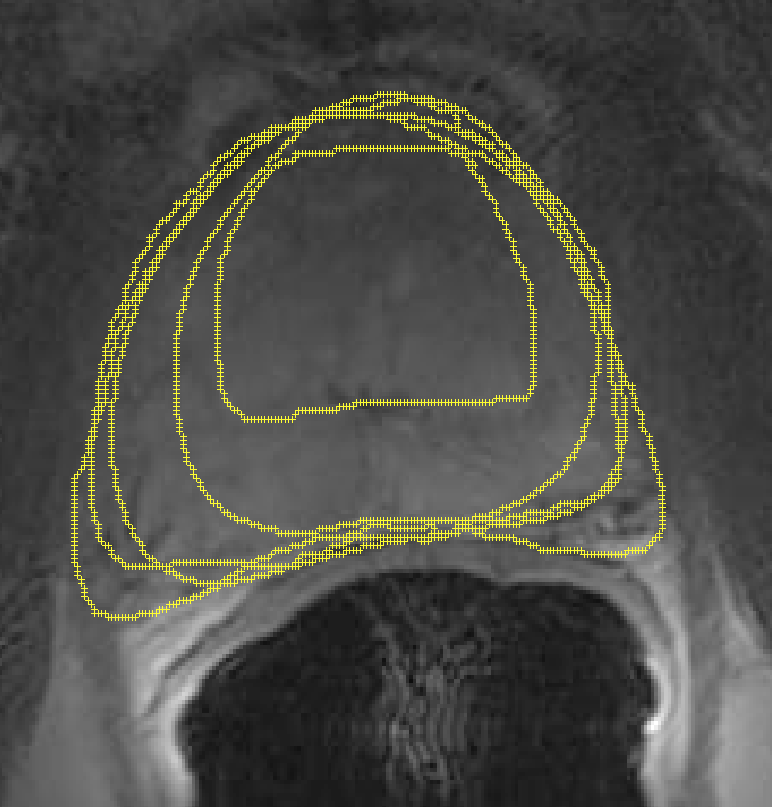

In the previous section, we simulated images in order to exploit “perfect segments”. In this section, we validate our approach using actual MR images of prostates. The image data from 15 patients were manually delineated by 5 oncologists.

The MR images used in this study were derived from an online database444http://prostatemrimagedatabase.com/. The database contains T2-weighted MR volume datasets, provided by Brigham and Women’s Hospital, the National Center for Image-guided Therapy, and Harvard Medical School. The images comprised T2-weighted MR images (T2W-MR) with endorectal coils. The pulse-sequence groups in the DICOM headers of most of the T2-weighted images were marked fast-spin echo (FSE), although some were marked as fast-relaxation fast-spin echo-accelerated (FRFSE-XL). The dataset contained images with slice thickness ranging from 2.5mm to 4.0mm, and varying contrast levels and signal-to-noise characteristics. All of the images were captured at a depth of 16 bits, and they varied in size from 256256 to 512512 pixels.

Sample images are depicted in Figure 6 (top row). Generally, one assumes that prostate segmentation is a relatively easy task. However, the variability of such segmentation remains considerable, and this is conspicuous in Figure 6 (bottom row).

We randomly selected 15 patients (out of more than 100) with a total of 558 slices, from which 145 slices were contoured by all 5 oncologists, resulting in a total of 725 segments555All DICOM images and their manual segmentations were provided by Segasist Technologies, Waterloo, ON, Canada.. Similar to the validation using simulated images, we first ran STAPLE on all user segments to generate a consensus for each slice. (Note that this is a “regular” consensus, insofar as all experts were available to mark the same image.) After we have the regular consensus, we can measure the agreement of each user using this consensus. This basically measures the extent to which each user has contributed to the consensus for that image. Table VII reports the results. From these results, User 3 is the most accurate666Theoretically, it is possible for four bad users to dominate the consensus, such that the fifth (excellent) user is understood as the worst. This is another reason to favor a large number of experts when building a consensus.. We selected User 3 as the gold standard. Then, we eliminated the segments from User 3 when building the atlas, in order to measure the accuracy of the computed consensus contours by comparing it against the manual delineations from User 3.